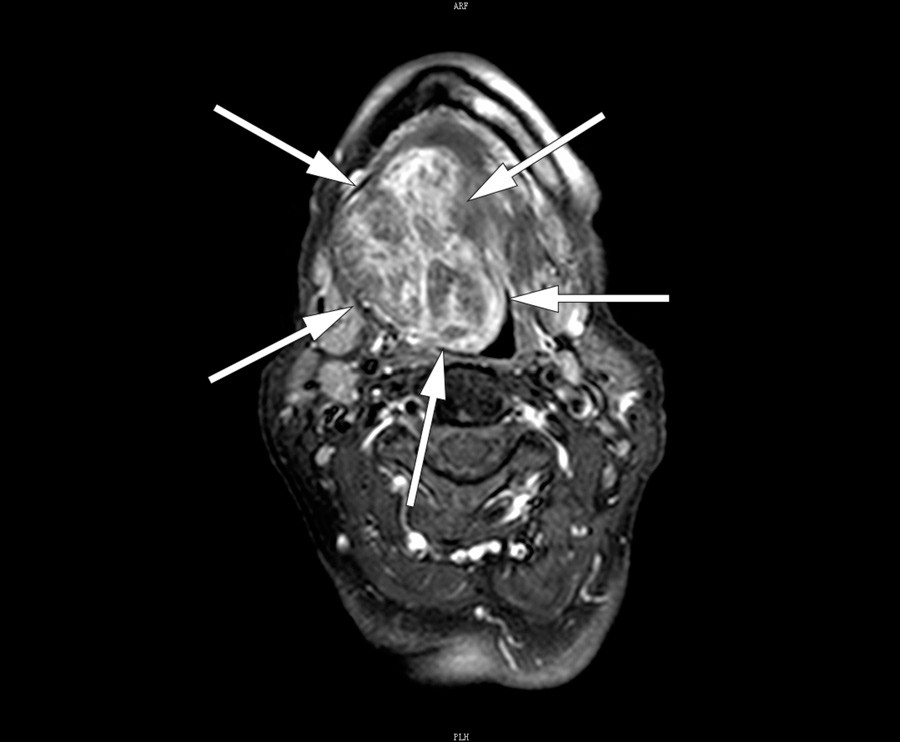

A CT neck scan using contrast medium (left) showed a large tumour in the floor of her mouth. An MRI neck scan with contrast (right) showed irregular contrast enhancement in the tumour. Fine-needle cytology revealed tissue most consistent with thyroid gland with no sign of malignancy. The findings indicated ectopic thyroid, and re-examination of the CT images showed an absence of thyroid tissue in the usual location. Blood tests showed that the patient was euthyreotic and negative for antithyroperoxidase and antithyroglobulin antibodies.